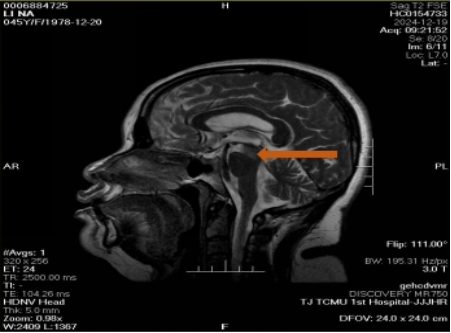

Acupuncture as an Integrative Therapy for Wallenberg Syndrome: A Case Report on Neurological Recovery

Rachana KC, Jin Xiaoxian, Wang Yuting, Du Yuzheng, Zhang Lil

A Case Report | 26 Sep 2025

Acupuncture as an Integrative Therapy for Wallenberg Syndrome: A Case Report on Neurological Recover...